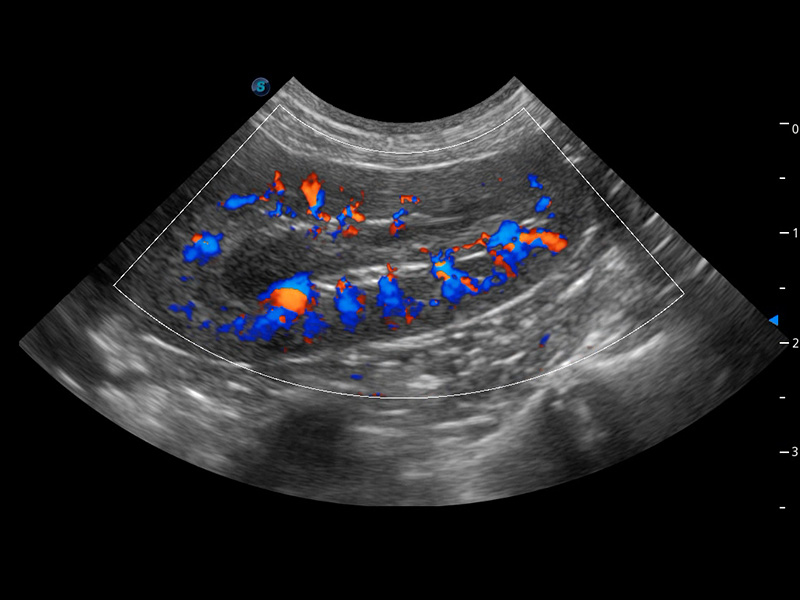

ProPet 60 作為一款高端臺式動物超聲設(shè)備,為動物醫(yī)生的日常診斷提供了一系列貼合動物臨床需求、解決臨床實際問題的高級成像功能。憑借全系列高清探頭,滿足醫(yī)生對腹部、心臟、生殖、淺表、肌骨等成像的所有需求,切實幫助您提升檢查效率,提高診斷信心。

動物是人類最親密的朋友和最值得信賴的伙伴。開立醫(yī)療也一直致力于探索動物專用的超聲影像解決方案。 全新推出的ProPet系列,是開立在動物超聲影像智能化、專業(yè)化、精準(zhǔn)化的一次跨越式革新。動物不能用言語來表述自己的不適,通過超聲影像,ProPet系列搭建了動物醫(yī)生與不同物種溝通的“橋梁”,為動物醫(yī)生注入了“治愈之力”。